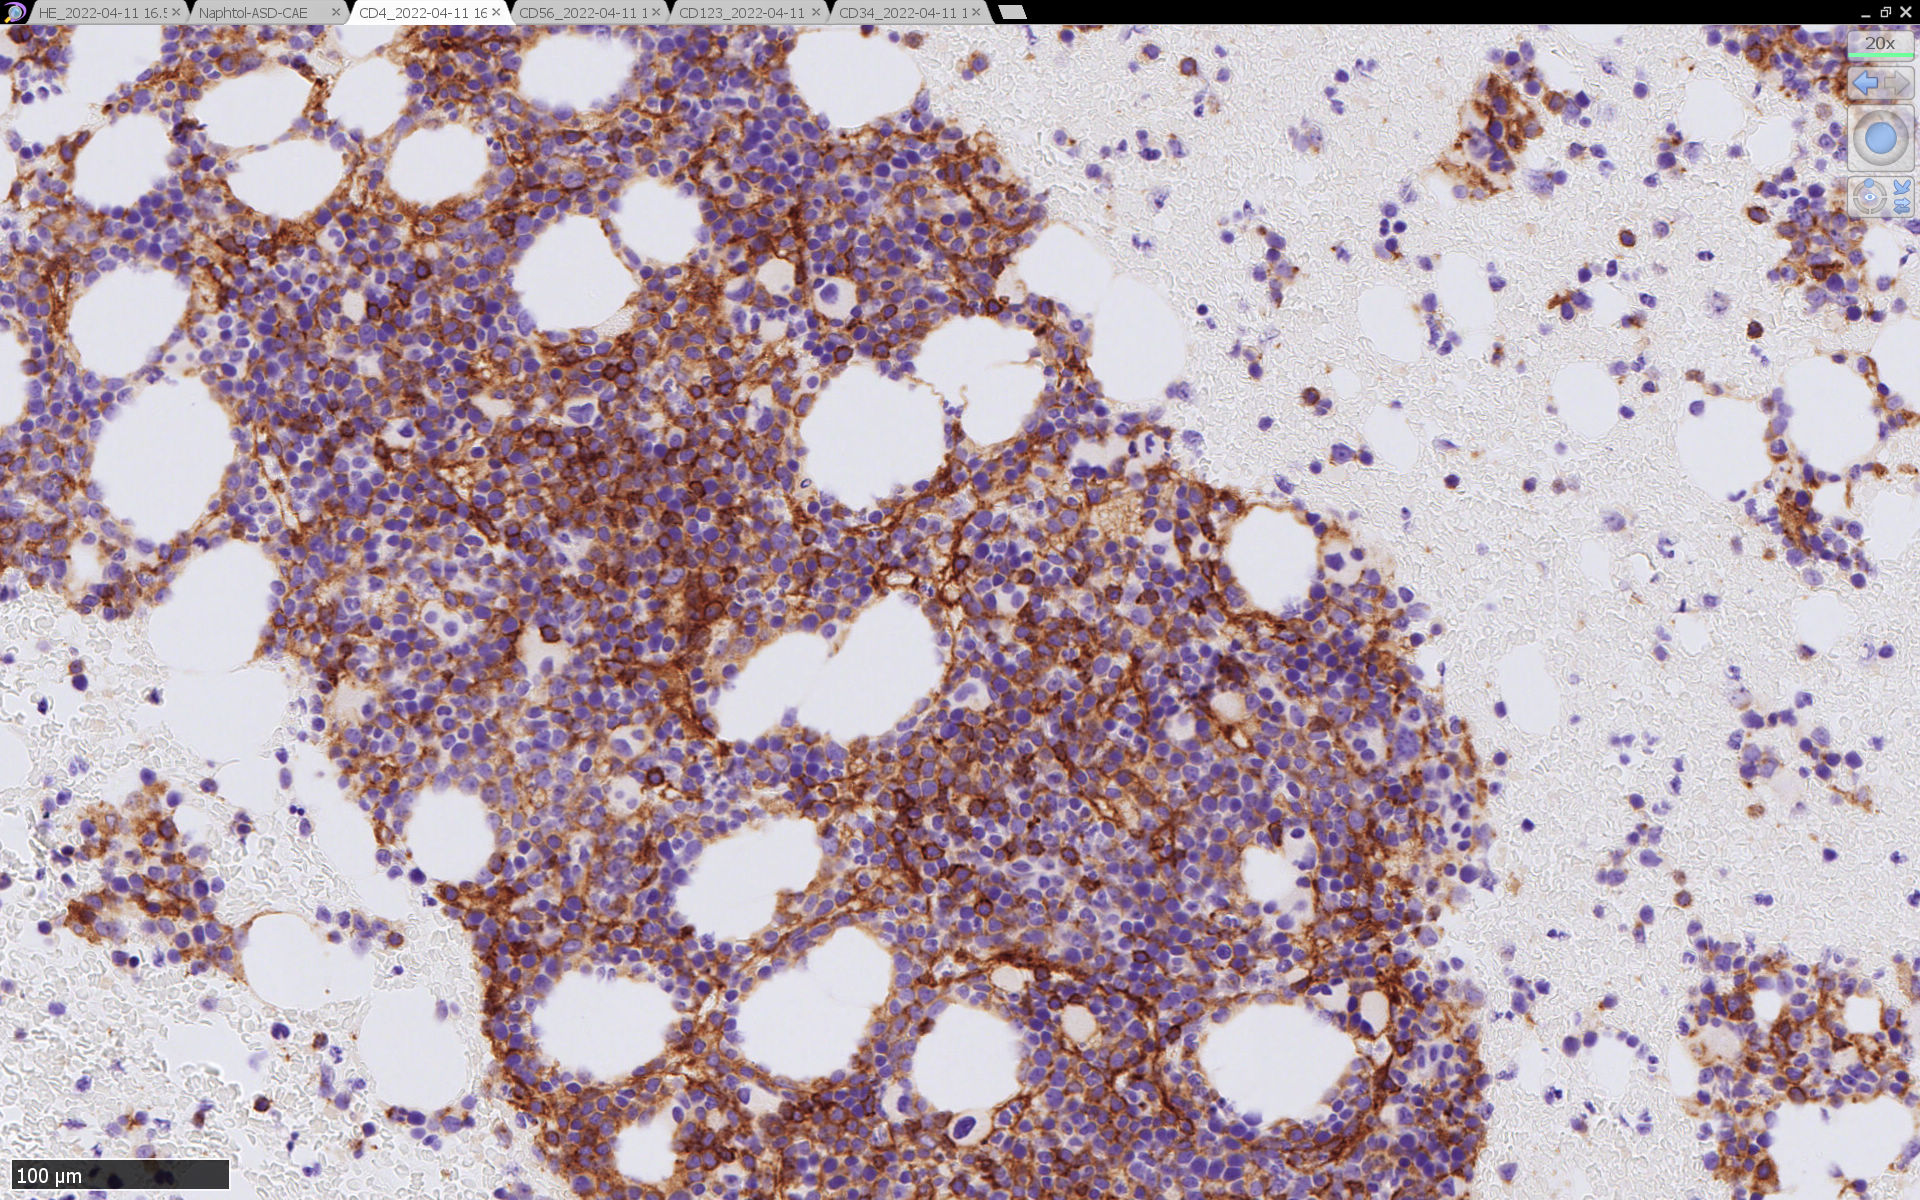

骨髄病理所見

HEでは腫瘍細胞の同定が難しい. 本症例は ASD-Giemsa染色を見ても, 腫瘍胞巣はよくわからなかった. 皮膚が先に診断がつき, 次いでBone marrowだったため, 免疫染色にすすめたが, Bone marrowが先だと診断に困ったかもしれない.

免疫染色

CD4は染まりすぎの感がある(濃く染まる細胞はCD4+ T-cellかもしれない). CD56, CD123が陽性で可能性が高くなり, BPDCNの診断にはCD34は陰性であることが必要

TCF4、CD123、TCL1をconsultationにより染色していただき, 陽性を確認した. CD34-, lysozyme-, CD123(おいてある病院は少ないかも)をしらべて, BPDCN研究会あてconsultationをする流れでしょうか.